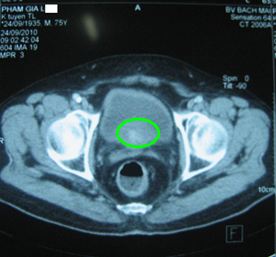

Chụp CT 64 dãy (MSCT) tiểu khung: Tuyến tiền liệt 3 x 4 cm, ước lượng 21g, không có khối khu trú, không ngấm thuốc bất th­ường, không xâm lấn túi tinh và bàng quang.

Sau điều trị 3 tháng

Tiểu tiện bình thư­ờng, không còn đái dắt

TTL: 3 x 4 cm; 21 g

PSA: 0,25 ng/ml